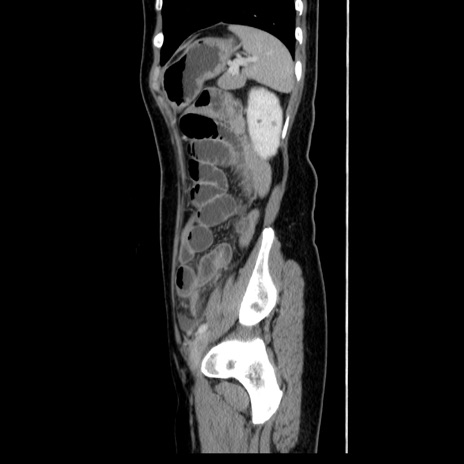

症例39(矢状断像)

【症例】40歳代女性

【主訴】上下腹部痛

【現病歴】2日目から下腹部痛あり。夜間は痛みで眠れなかった。昨日より上腹部痛と下痢が出現。臥位で痛みは軽快したため、休んでいた。本日になって臥位でも立位でも痛みが強くなってきたため救急要請。

【既往歴】子宮内膜症

【身体所見】部:平坦・軟、左上下腹部に圧痛あり、反跳痛あり。

【データ】WBC 21800、CRP 26.78

CT